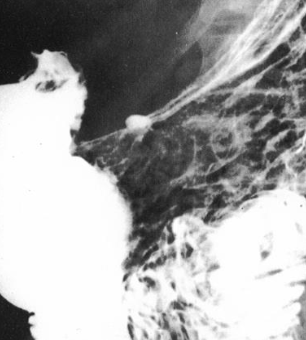

Neoplasm esofagian malign infiltrativ

Neoplasm esofagian malign vegetant

Neoplasm faringo-esofagian malign

Neoplasm esofagian malign